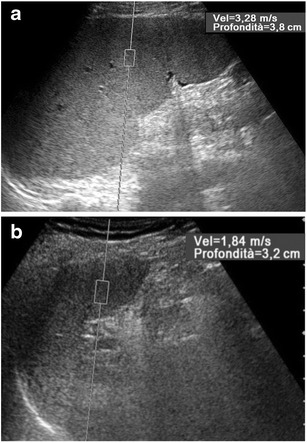

Fig. 11.

ARFI evaluation of the spleen in patients with alcoholic liver cirrhosis. Longitudinal US scans. The SWV value is lower (1.84 vs. 3.28 m/s) in a 54-year-old man with Child-Pugh score A (a) than in a 51-year-old man with Child-Pugh score C (b), with severe portal hypertension and recurrent variceal bleeding